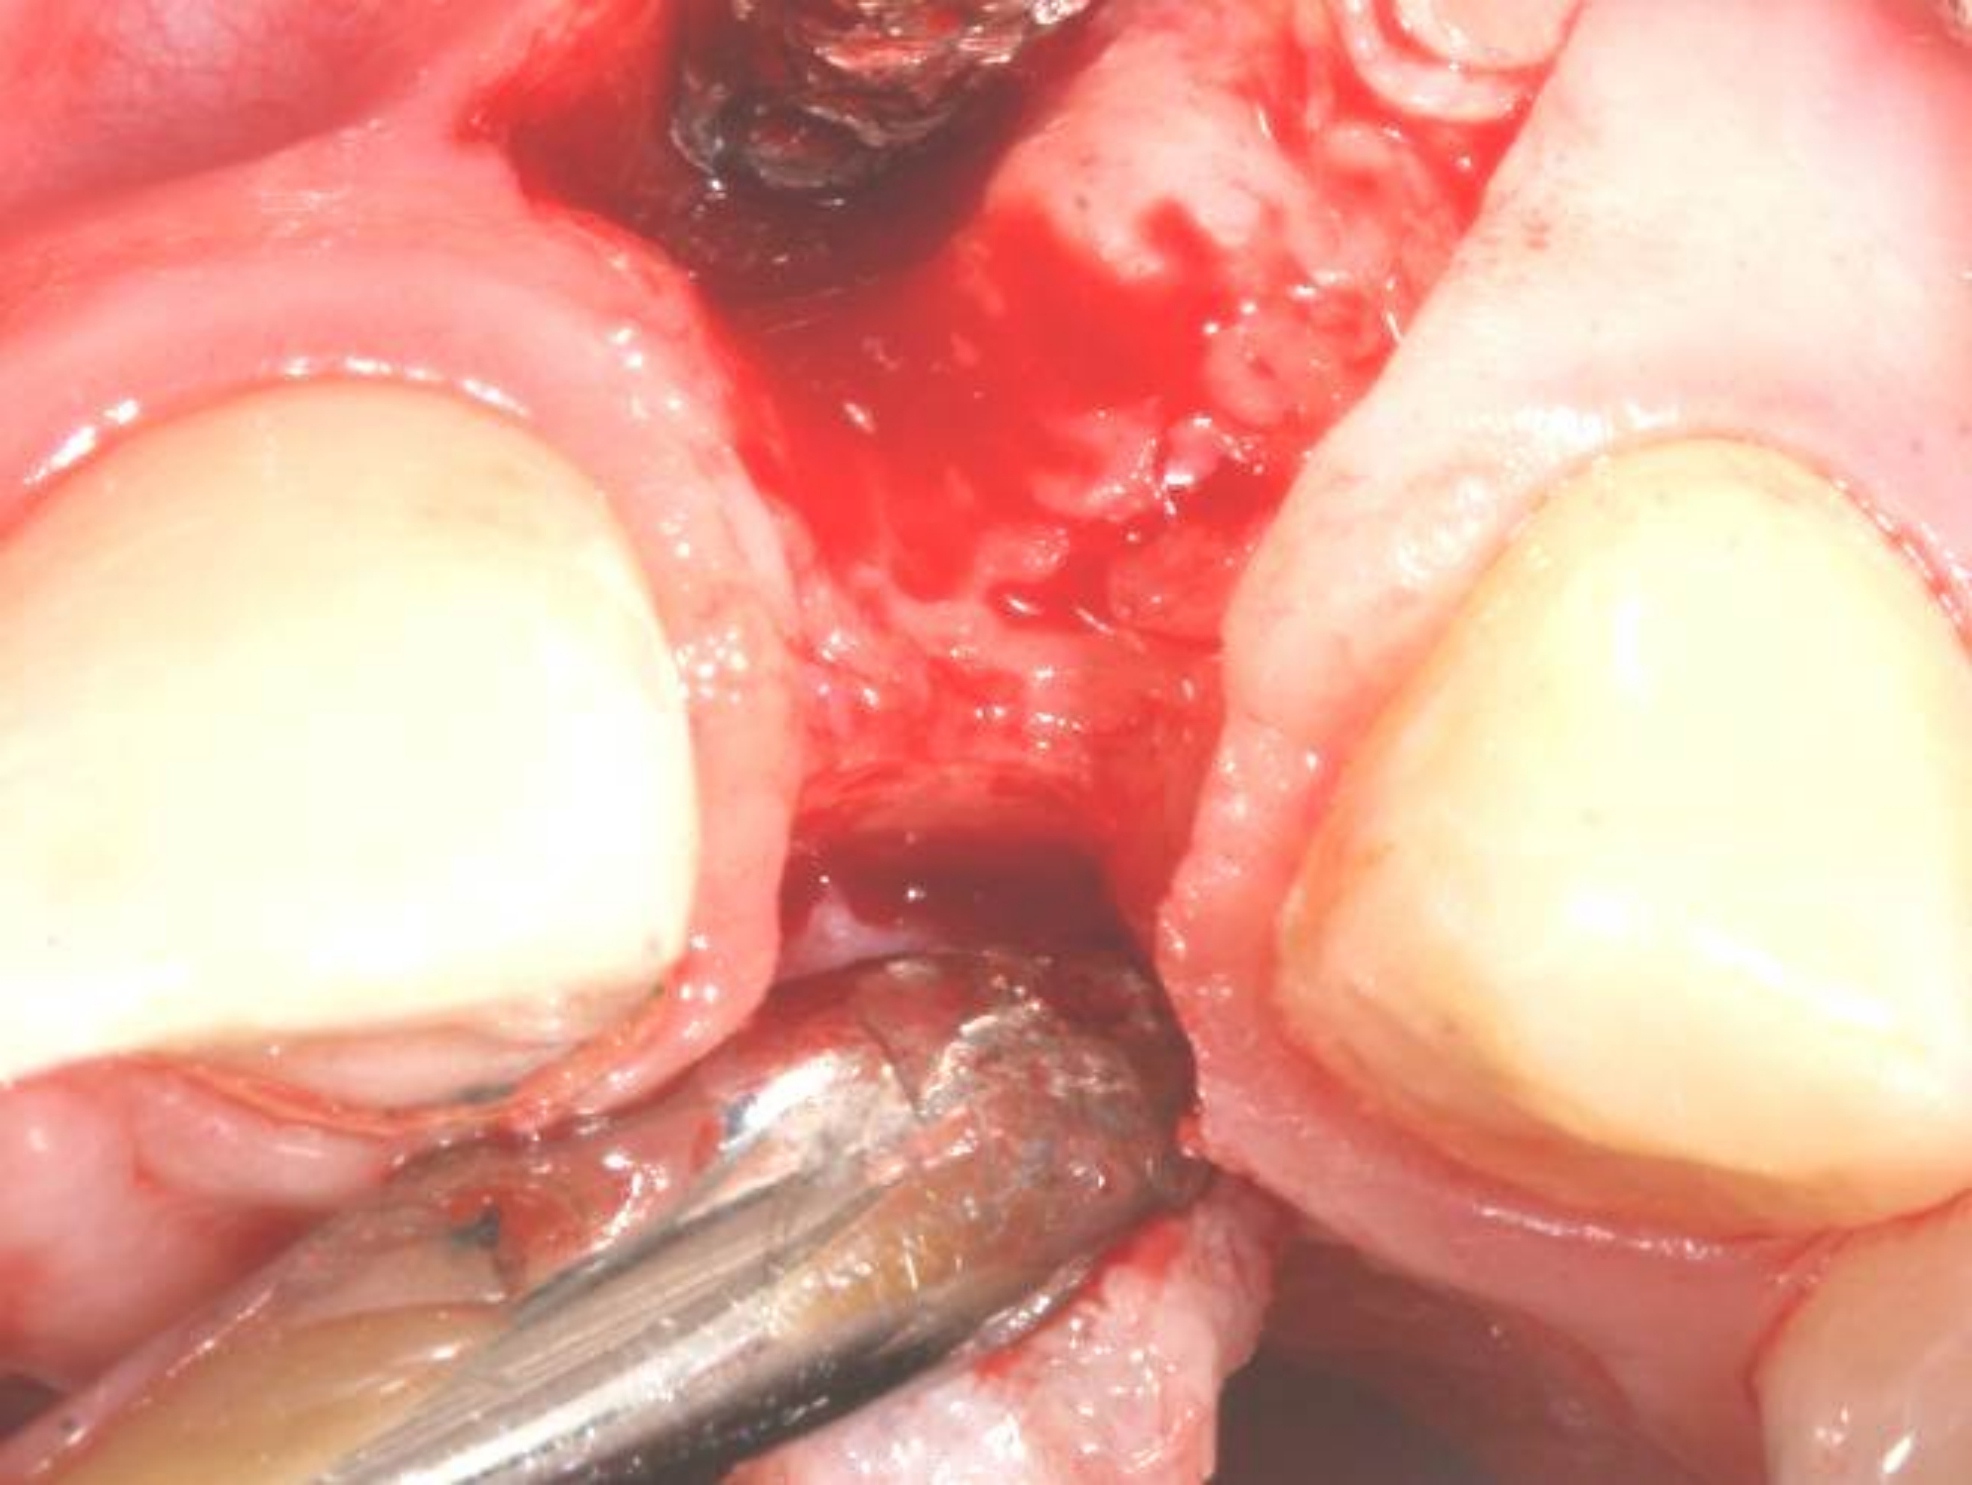

Fig 13. A buccal pedicle flap was elevated, exposing the buccal bony plate.

Figure 13

Fig 14. Implant placed into the thin ridge of bone, occlusal view.

Figure 14